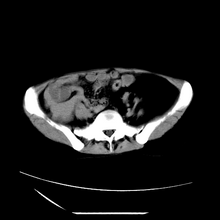

女性,41岁,发现左腹部包块3年,现行ct检查,检查前做过静脉肾盂造影。

左侧低密度区是脂肪密度,中间可见条索状软组织样密度影,现主要想知道左肾前下缘圆形软组织样密度影,内见低密度水样密度影,这是什么?

脾脏增大,左肾后方脂肪增多,脊柱前方脂肪增多,左肾窦脂肪增多,左肾变形,双肾积水以左侧为著,左肾内侧及上方见环形软组织肿物影,内部低密度区,考虑1盆腹腔/腹膜后及左肾窦脂肪增多症2左肾内侧病灶可能为左肾上腺病灶,可能为脂肪增多的原凶

1)考虑左肾替代性脂肪瘤病;不排除左肾错构瘤。2)双肾积水。